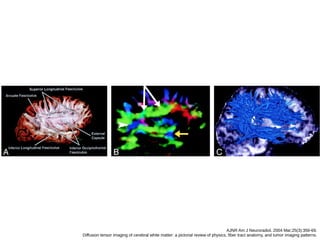

Fascículo longitudinal superior

(arqueado)

● Trato massivo de fibras que seguee junto da

margem superior da ínsula em um grande arco,

onde libera fibras no seu caminho, que

conectam o lobo frontal, parietal, temporal e

occipital.

AJNR Am J Neuroradiol. 2004 Mar;25(3):356-69.

Diffusion tensor imaging of cerebral white matter: a pictorial review of physics, fiber tract anatomy, and tumor imaging patterns.

Fascículo longitudinal inferior

(occipitotemporal)

● Conecta o lobo temporal e occipital, um trato

transverso ao lobo temporal e se conecta ao

fascículo occipitofrontal inferior, e as radiações

ópticas para formar o stratum sagittal.